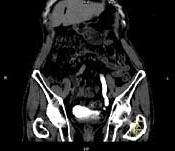

问题 男,76岁,无痛性肉眼血尿3个月,CT检查如图所示,下列说法错误的是 ( )

选项 A、考虑为左侧输尿管炎 B、考虑为左侧输尿管下段癌 C、左侧输尿管中上段扩张 D、左侧输尿管下段可见节段状不规则的软组织肿块影 E、左侧肾盂扩张积水

答案 A